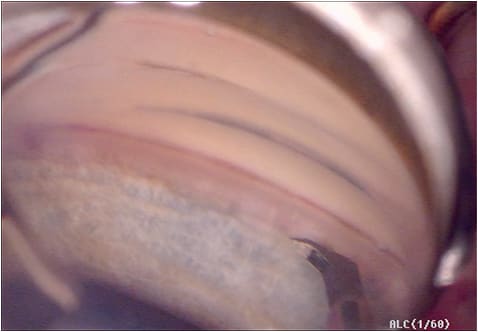

The gonioscopy-assisted transluminal trabeculotomy, or GATT procedure, is a minimally invasive, ab-interno approach to a circumferential 360-degree trabeculotomy. This procedure is performed in a similar manner as the ab-interno canaloplasty, but instead of slowly withdrawing the catheter, the leading edge is grasped and externalized, which creates the first half of the trabeculotomy. Traction is then placed on the trailing end of the catheter to complete the 360-degree trabeculotomy.